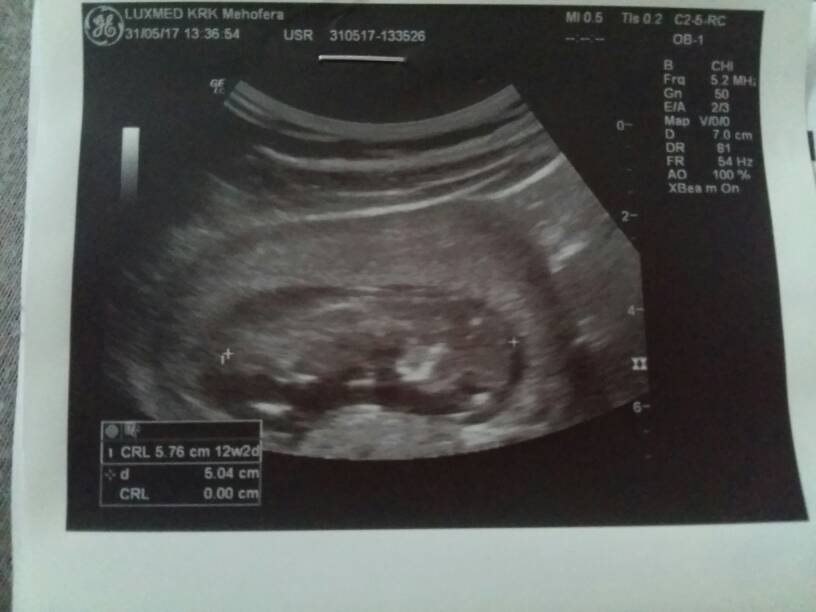

Uparte stworzenie nie chciało współpracować,bo się przecież wyspać musi, ale udało się sprawdzić co najważniejsze. Wielkość 5.92 cm, Przezierność książkowa, kość nosowa - jest, serduszko biło 160/min, móżdżek piękny, oczka najsłodsze na świecie, rączki dwie są, nóżki tak samo, widzieliśmy pęcherz i żołądeczek. Przepływy krwi w porządku. Krótko mówiąc bardzo niskie ryzyko wad genetycznych, Fistaszek jest zdrów jak rybka. Terminy nam się troszkę pozmieniały: OM 11.12.2017, USG 12.12.2017, więc zaraz zrobię poprawki w kalendarzu. Kolejna wizyta 31.07, ale będę patrzeć - może coś się zwolni parę dni wcześniej

Zdjęcia: